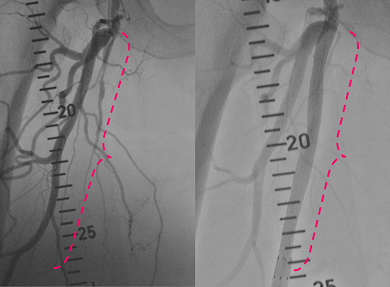

図の説明

左 ピンクの点線部の血管(浅大腿動脈)が閉塞しています。

右 ステントを留置して血流が改善しました。